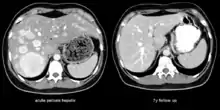

Peliosis hepatis is an uncommon vascular condition characterised by multiple, randomly distributed, blood-filled cavities throughout the liver. The size of the cavities usually ranges between a few millimetres and 3 cm in diameter.[1] In the past, it was a mere histological curiosity occasionally found at autopsies, but has been increasingly recognised with wide-ranging conditions from AIDS to the use of anabolic steroids. It also occasionally affects spleen, lymph nodes, lungs, kidneys, adrenal glands, bone marrow, and other parts of gastrointestinal tract.[2]

The condition is typically asymptomatic and is discovered following evaluation of abnormal liver function test. However, when severe, it can manifest as jaundice, hepatomegaly, liver failure, and haemoperitoneum.